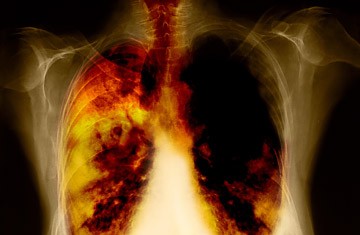

Αύξηση στους θανάτους από καρκίνο των πνευμόνων προβλέπει για πρώτη φορά φέτος μια νέα ιταλοελβετική επιστημονική έρευνα, καταλαμβάνοντας την πρώτη θέση σε σχέση με τους θανάτους από καρκίνο του μαστού, μεταξύ των γυναικών στην Ευρώπη. Διαβάστε περισσότερα στο boro.gr